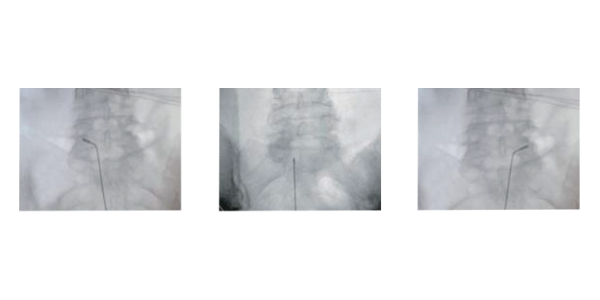

Die Elektrode ist vollständig navigierbar und flexibel konzipiert. Dies erlaubt dem Chirurgen eine präzise Führung unter fluoroskopischer Kontrolle, selbst in anatomisch anspruchsvollen Bereichen des Wirbelkanals.